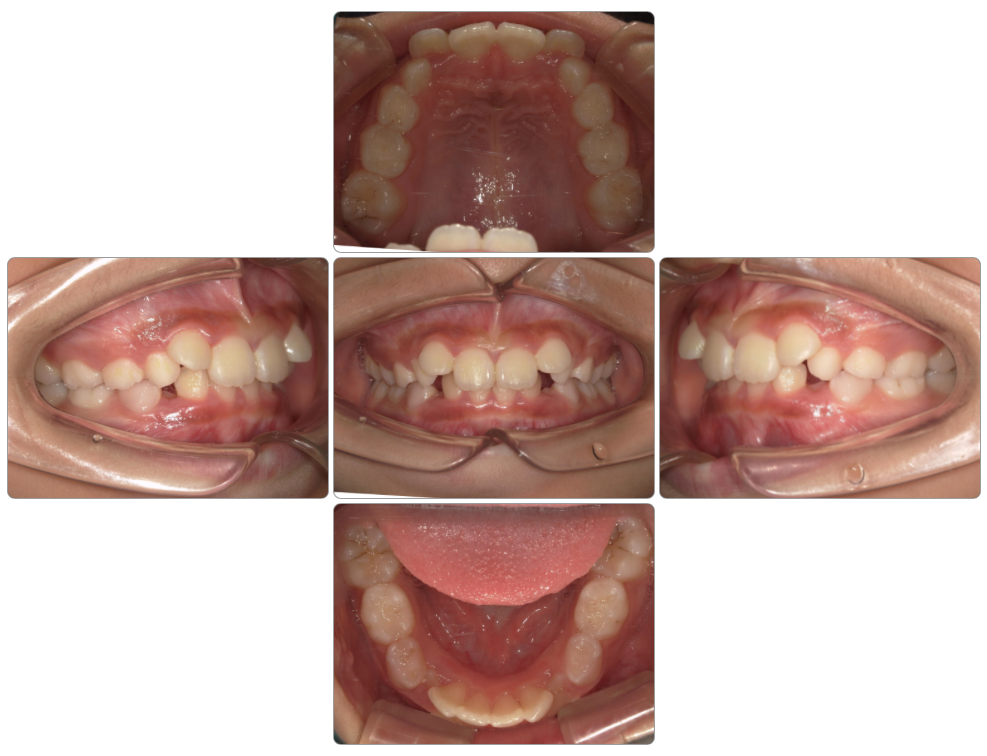

上顎前突の治療例

Before

after

| 初診時 | 8歳1か月 |

| 治療期間 | 2年2ヵ月 |

| 費用 | ¥550,000 調整料・¥5,500/月 |

| 使用装置 | マイオブレイス・BWS |

| リスクと副作用 | |

| 原因と考察 | 頚椎成長が足りないために下顎骨の高さが育っていません。このことが口腔の高さが不足しています。マイオブレイスを使用していると厚みがある分下顎骨の高さがますのでこのように過蓋咬合が改善に導かれます。ただ全身の問題で考えると頚椎成長を促すような生活指導は原因除去という点では欠かせません。 |